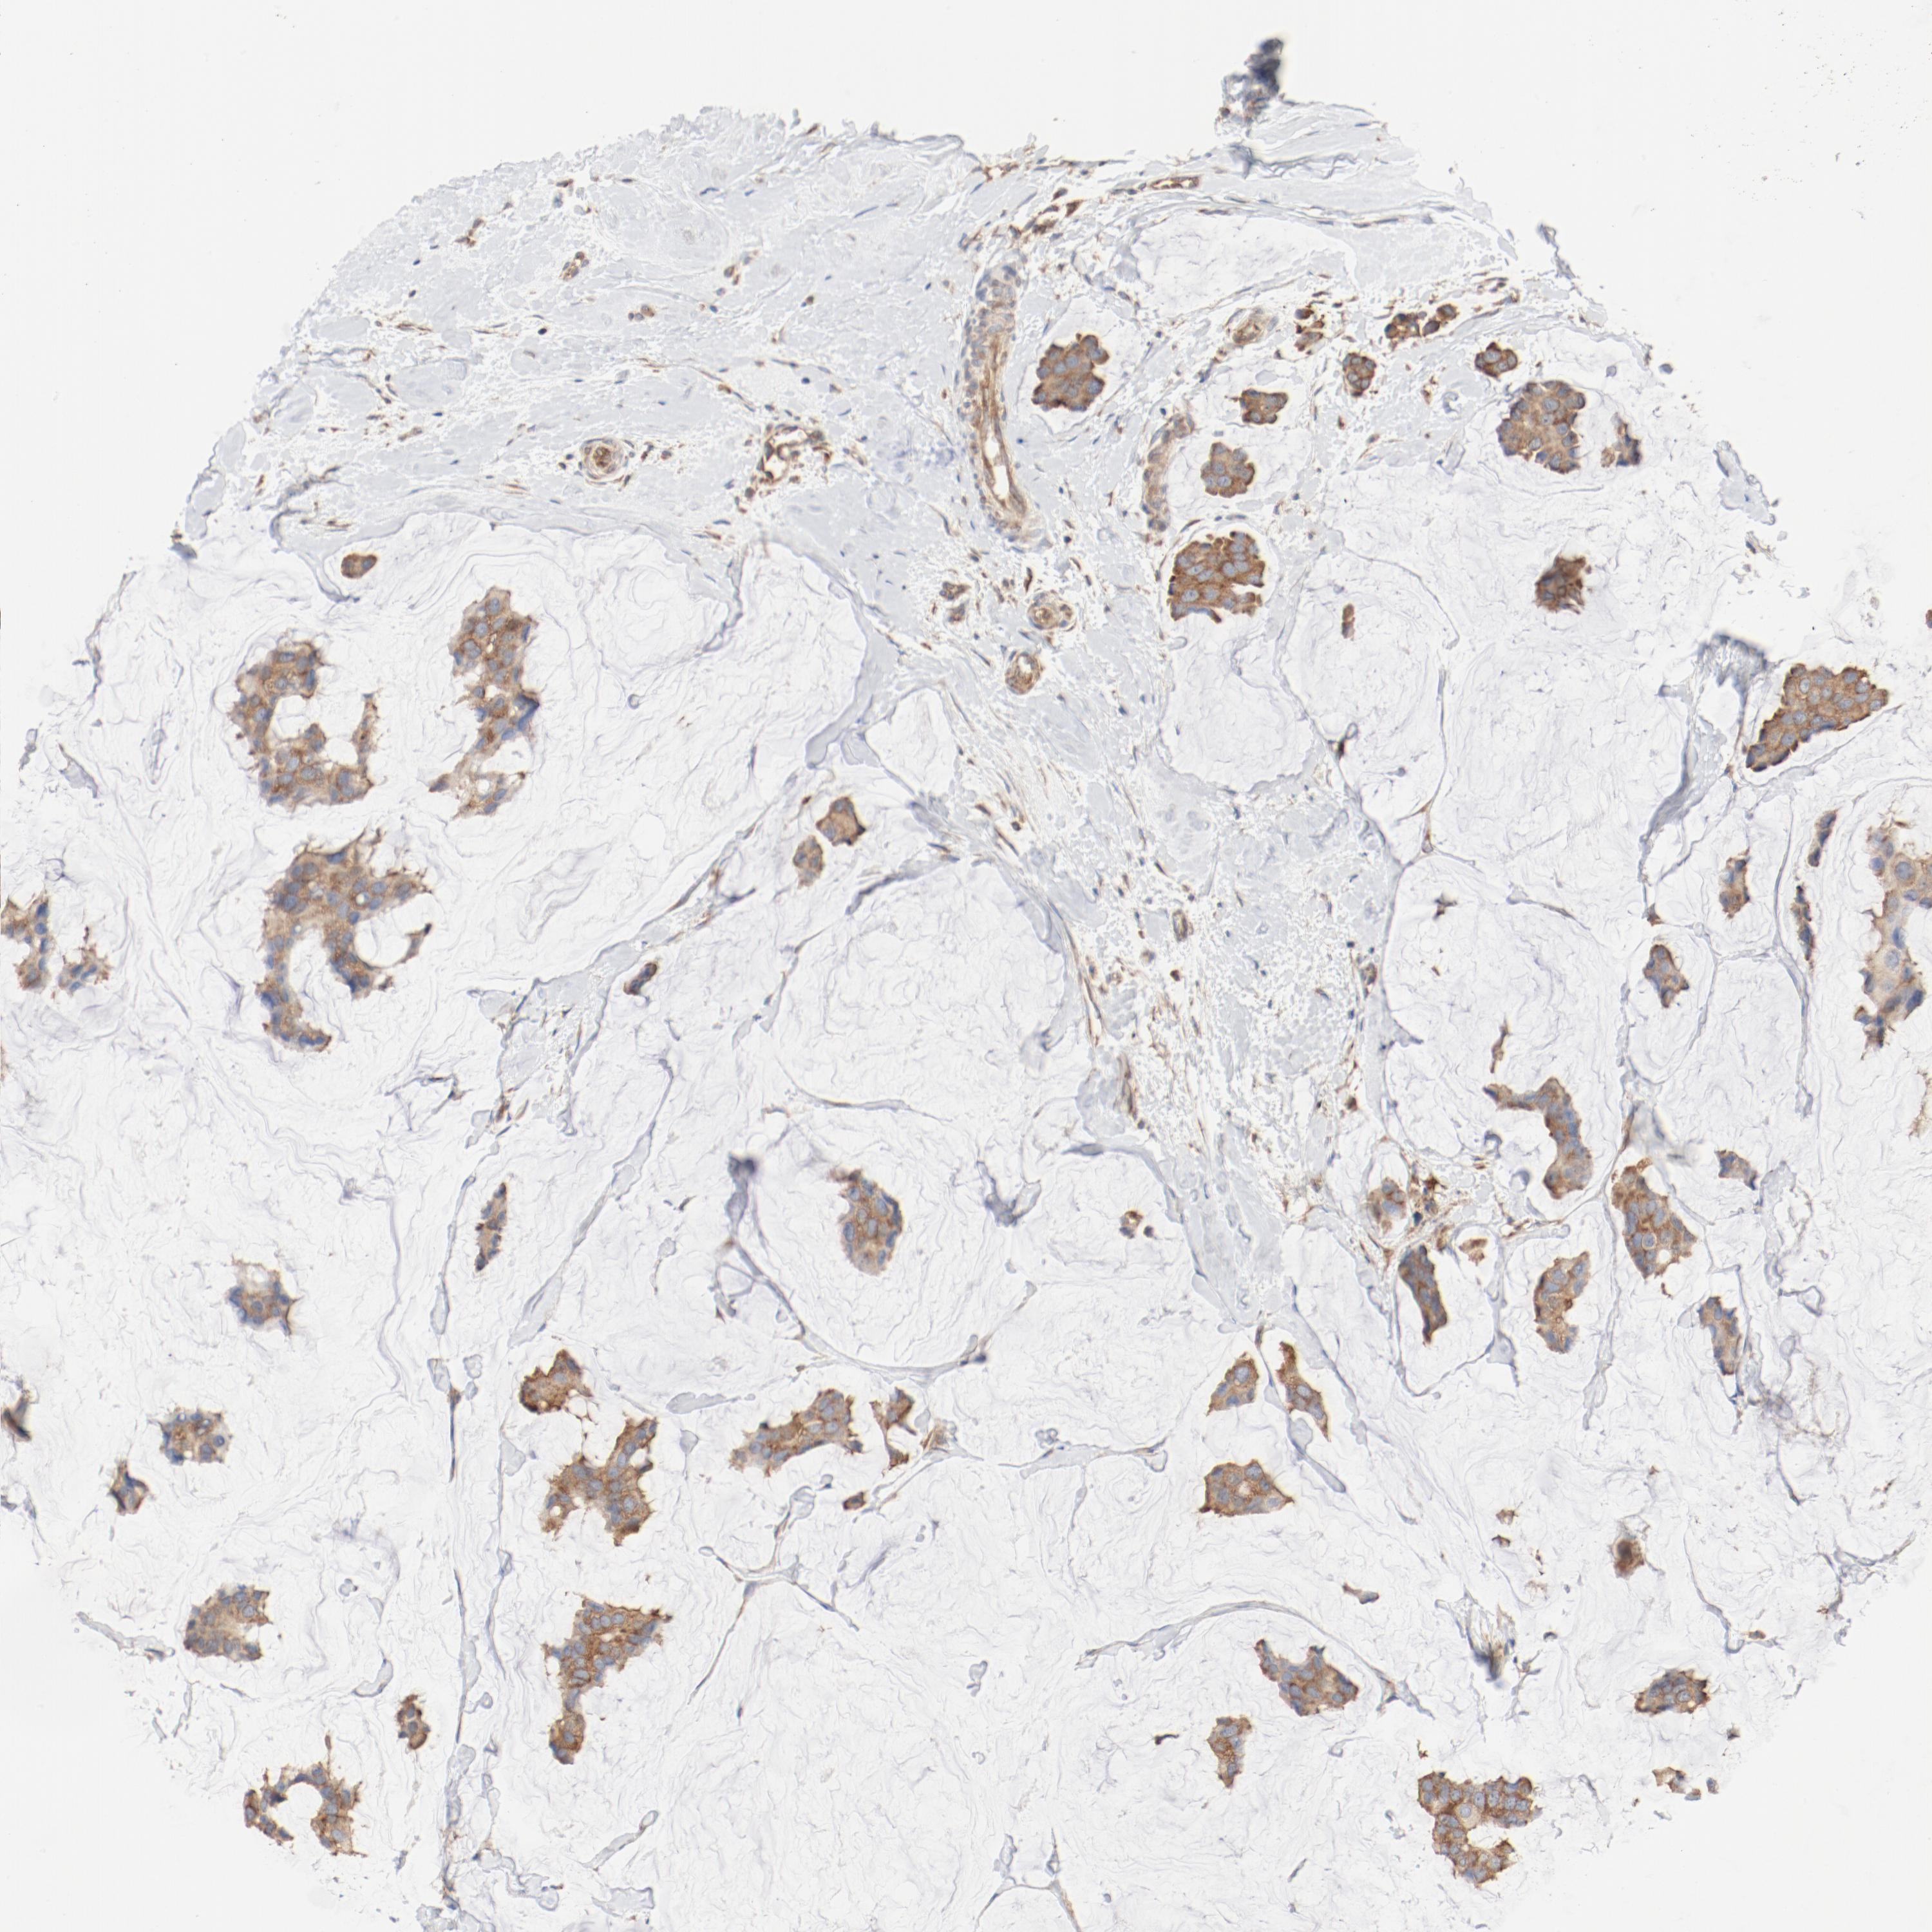

CANCER BREAST CANCER Show tissue menu

BRCA TCGA BRCA VALIDATION PROTEIN EXPRESSION